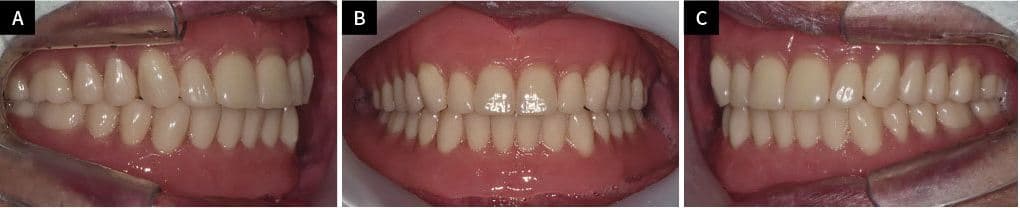

REAL PATIENT RESULTS

To'liq implant

oldin va keyin

Haqiqiy bemorlarimizning ajoyib o'zgarishlarini ko'ring

DENTURE CASES

Protez oldin va keyin

Tabiiy va qulay protez bilan

hayot sifatini oshiring

After ✨

Kim●● · 70 yoshdan oshgan ayol

Yuqori va pastki to'liq protez

Park●● · 80 yoshdan oshgan erkak

Lee●● · 70 yoshdan oshgan ayol

Yuqori to'liq protez + Pastki implant qisman protez

Aniq moslashtirilgan protez ishlab chiqarish

Shifoxona laboratoriyasida bemor uchun maxsus ishlab chiqarilgan

Tabiiy milk rangi va tish joylashuvi

Qulay kiyish, erkin ovqatlanish va gaplashish

Implant bilan birgalikda barqaror mahkamlash mumkin